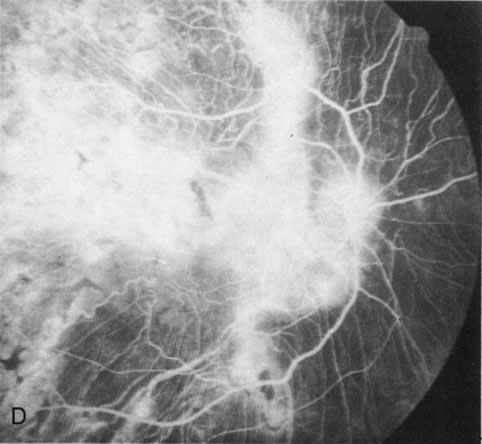

Fig. 1. Retinitis pigmentosa. A. A typical area of bone spicule pigmentation. B. Diffuse dye leakage is apparent throughout the posterior pole. C. The early angiogram shows dilated and irregular retinal radial peripapillary capillaries and perifoveal retinal capillaries. D. Leakage from these vessels are evident in the late angiogram.

Dye leakage in RP may occur from the retinal vessels or at the level of the retinal pigment epithelium (Fig. 1B).2–4 The leakage may be seen in the macula and posterior pole, along the vascular arcades in the distribution of the radial peripapillary capillaries, and in the periphery (where an exudative vasculopathy resembling Coats' disease is suggested).

Of more clinical importance is the role of FA in the diagnosis and treatment of cystoid macular edema (CME) (Fig. 1C and D). Stereoscopic FA indicates that the leakage, which may be diffuse or have the typical petaloid stellate appearance of CME, can come from the perifoveal retinal capillaries, from the choroid through the RPE, or from a combination of both sources.4 With the recent suggestion that CME in RP may be successfully treated with acetazolamide,5, 6 FA is thus important to document the diagnosis of CME, establish the origin(s) of leakage, and follow patients during and after therapy.